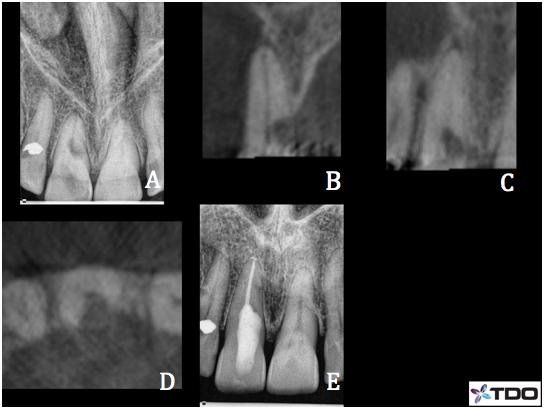

Case 1-#27 Class III ECIR with external surgical repair

63 y/o female presented to our office for the evaluation of tooth #27. B root surface filling placed many years ago and current dentist suspected resorption after raising an exploratory flap. Patient was asymptomatic. Radiographic and CBCT exams reveal a B surface composite filling surrounded by what appears to be an ECIR Class III. CBCT reveals the resorption extends into the coronal 1/3rd of the root and to within close proximity of the pulp (B). No evidence of periapical bone loss and apical tissues appear WNL. The tooth responded WNL to cold testing and pulp was vital. B surface access was made because the tooth was partially rotated, making the lingual surface unavailable for traditional access. Pulpectomy was completed and the canal was medicated with Ca(OH)2. Patient returned 4 weeks later for the completion of RCT (C,D). The coronal 1/2 of the canal was filled with with Geristore (blue highlight) so that excavation of the external resorption resulted in contact with glass ionomer material rather than gutta percha. B access was restored with flowable composite (purple highlight). A sulcular flap was raised and the existing composite and the ECIR lesion was debrided. The prep was soaked with 90% trichloracetic acid and then restored with Geristore (E). The flap was re-approximated and sutured in place with 5-0 interrupted vicryl sutures. Patient remained asymptomatic at her 6 months recall(F). Soft tissues appeared WNL. No gingival swelling. Perio probings were 1-2mm and WNL. Apical tissues appeared normal.